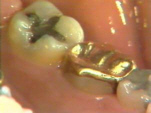

| Aquí puede verse la

permanencia de cálculo al separar con aire el tejido gingival. Este cálculo está

muy alejado para ser eliminado por un instrumento ultrasónico o un instrumento de

mano. Los estudios han mostrado que es prácticamente imposible quitar todo el cálculo

subgingival. A pesar de esto en la mayoría de los casos los tejidos sanan

satisfactoriamente con un tratamiento subgingival cuidadoso. |

Después de 2 meses del

tratamiento la gingiva es saludable y las profundidades de los

surcos (bolsas) periodontales están reducidas. No se observa

sangrado al sondaje. |

| Fotografía anterior al

tratamiento, que sirve como comparación. Hay abundante placa y bolsas

periodontales profundas. |